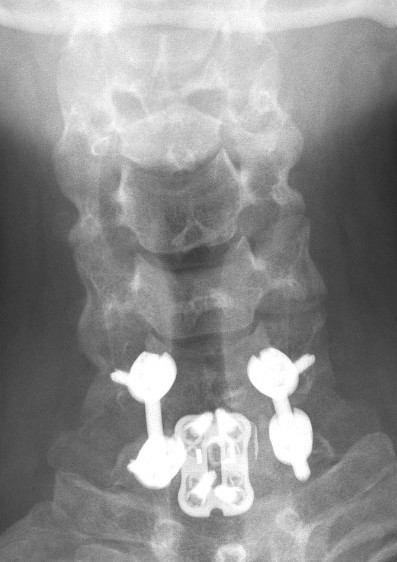

Management

Urgent reduction

- tongs

- GA

Anterior +/- posterior fixation